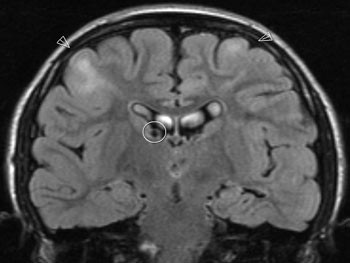

Hos om lag 95 % av pasientene med syndromet er det forandringer i sentralnervesystemet (7). Det er ved MR-teknikk funnet fire typer forandringer i hjernen: kortikale og subkortikale tubera, subependymale knuter (fig 4), kjempecelleastrocytomer og migrasjonslinjer i hvit substans. Antall tubera varierer, størst antall finnes frontalt, deretter temporalt, parietalt og oksipitalt. Tubera kan forekomme i cerebellum. De er til stede ved fødselen, vokser ikke og øker ikke i antall. Tubera ses lettest på MR-bilder med FLAIR-teknikk. Histologisk undersøkelse av tubera viser distinkte karakteristika, som ødelagt cellearkitektur og laminering, variabelt celleinnhold og oppblåste astrocytter med store og/eller multiple kjerner (ballongceller). Pyramidecellene ligger rotete til og viser degenerative forandringer (8).

Subependymale knuter er rester av gliaceller som har stoppet i vandringen fra matriks. De er lokalisert til ventrikkelveggen, hyppigst mellom nucleus caudatus og thalamus. Knutene har meget stor affinitet til kalk og er derfor lett synlige på CT-bilder. Størrelsen varierer fra få millimeter til noen centimeter. De opptrer hos ca. 80 % av pasientene. En subependymal knute kan vokse utover sin opprinnelige begrensning og danne et kjempecelleastrocytom. Dette skjer hos 10 – 15 % av pasientene, hyppigst ved slutten av første dekade. Evnen til å vokse på denne måten avtar først når pasienten når 20 – 30 års alder (9). Skjer dette med knuter som ligger nær foramen Monroi, kan det oppstå en kompromittert sirkulasjon av cerebrospinalvæsken og dermed økt intrakranialt trykk. Trykksymptomer, nye fokalnevrologiske utfall og forverring i anfallssituasjonen skal vekke mistanke om en slik utvikling. En slik tilstand må vurderes med tanke på nevrokirurgisk behandling. Svulstene residiverer sjelden. Radiale migrasjonslinjer i hvit substans er et radiologisk fenomen som påvises ved MR-undersøkelse. Det skyldes dysplastiske nevroner og gliaceller som har stoppet opp i vandringen mot cortex. Histologisk ses likhetstrekk med tubera.